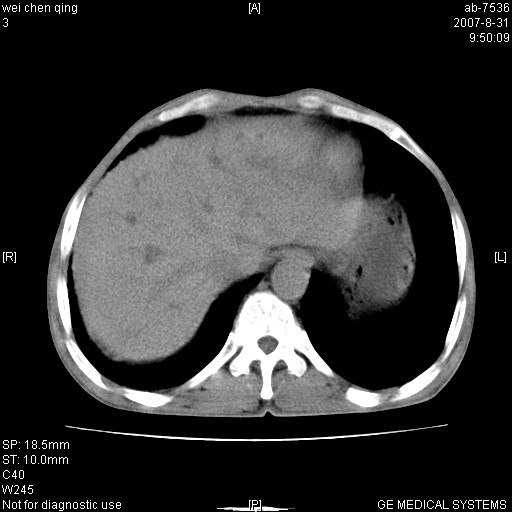

以下是引用zyyzzy在2007-8-31 14:34:00的发言:[br]该病人肝内胆管扩张,胆囊及胆总管未见明显扩张。在倒数第9层图像上可看到左右肝管结合部(肝总管)有软组织影,此处应薄层扫描。考虑肝总管占位(ca)、腹水。[br]